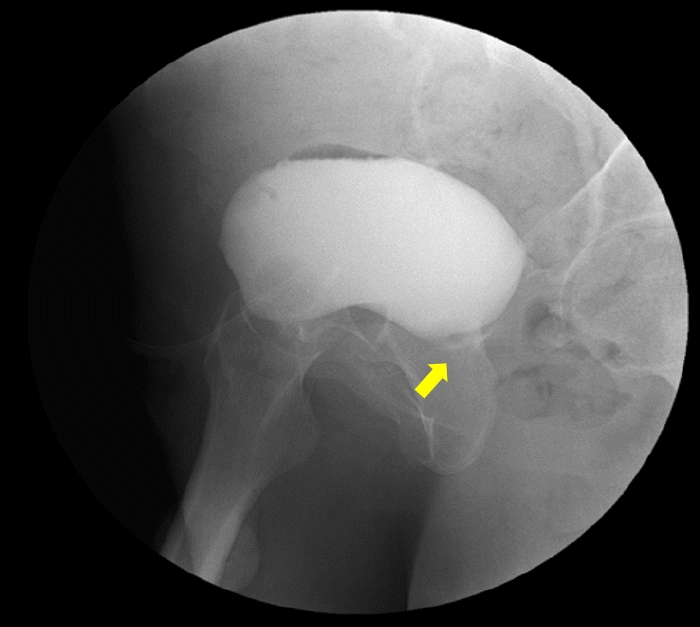

Laboratory findings revealed a white blood cell (WBC) count of 13,500/mm3, hemoglobin 9.5 g/dL, platelet count 207,000/mm3, C-reactive protein (CRP) level 22.91 mg/dL, procalcitonin > 100 ng/mL, blood urea nitrogen 44.7 mg/dL, serum level of creatinine 10.03 mg/dL, total CO2 content 24.4 mmol/L, random blood glucose 719 mg/dL, and hemoglobin A1C 8.0%. Routine urinalysis showed bloody and turbid urine with > 100 red blood cells per high power field (HPF), 31-50 WBCs/HPF, and mild bacteriuria. Initial plain radiography revealed multiple focal opacities in both lung fields and foci of air accumulation behind the pubic ramus. A subsequent abdominal computed tomography (CT) scan displayed multiple air foci in the prostate gland and bilateral seminal vesicles, with thickened urinary bladder walls indicative of emphysematous prostatitis with cystitis (Fig. 1). A chest CT scan demonstrated multifocal consolidations and groundglass opacities, likely due to septic embolic pneumonia (Fig. 2).

Figure 1.

Abdomen-pelvis CT obtained upon admission shows multiple air foci in the prostate gland and bilateral seminal vesicles (arrows), indicating emphysematous prostatitis with an abscess. CT, computed tomography.